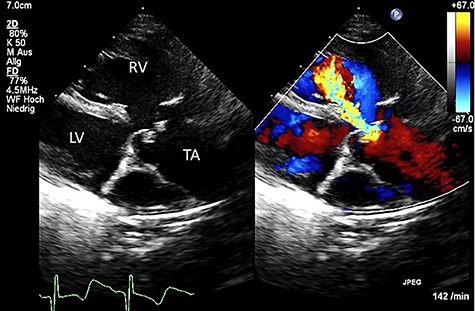

We present a case of a female patient referred at 10 days of age with 22q11.2 deletion syndrome, TAC type A2 of the van Praagh classification with a regurgitant, quadricuspid TV and VSD (Fig. 1). The patient had signs of heart failure and respiratory insufficiency and had to be intubated and transferred to the pediatric intensive care unit pre-operatively. After hemodynamic stabilization, surgery was performed.

Color Doppler echocardiography in the parasternal long axis view shows severe TV regurgitation. RV: right ventricle, LV: left ventricle, TA: truncus arteriosus.